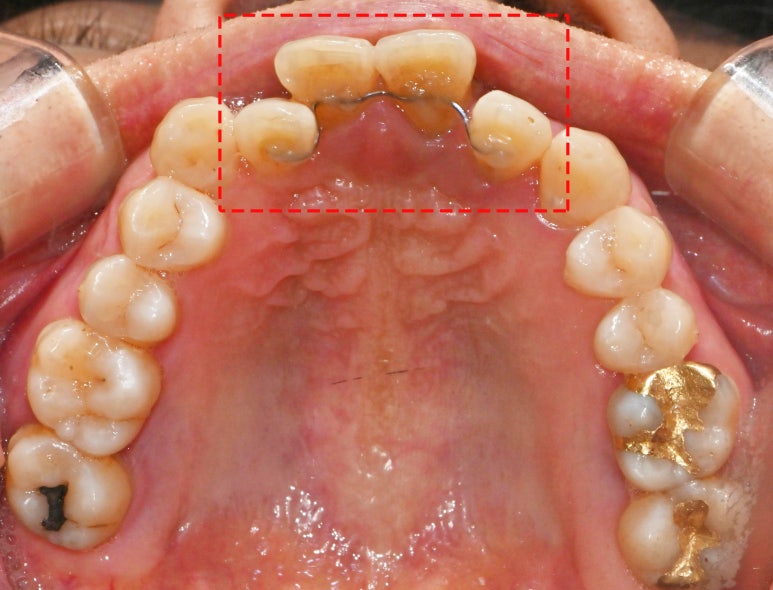

교합면에서 살펴보면

안쪽에 철사 같은 게 덧대어있죠?

이 환자는 위아래 반대교합되고 있는 치아의 이동이

시간이 지날수록 점차 심화되는 것 같아

우선 저렇게 유지 장치를 부착해두었습니다.

그렇게 하면 조금이라도

이가 더 많이 이동해버리는 것을

막을 수 있으니까요.